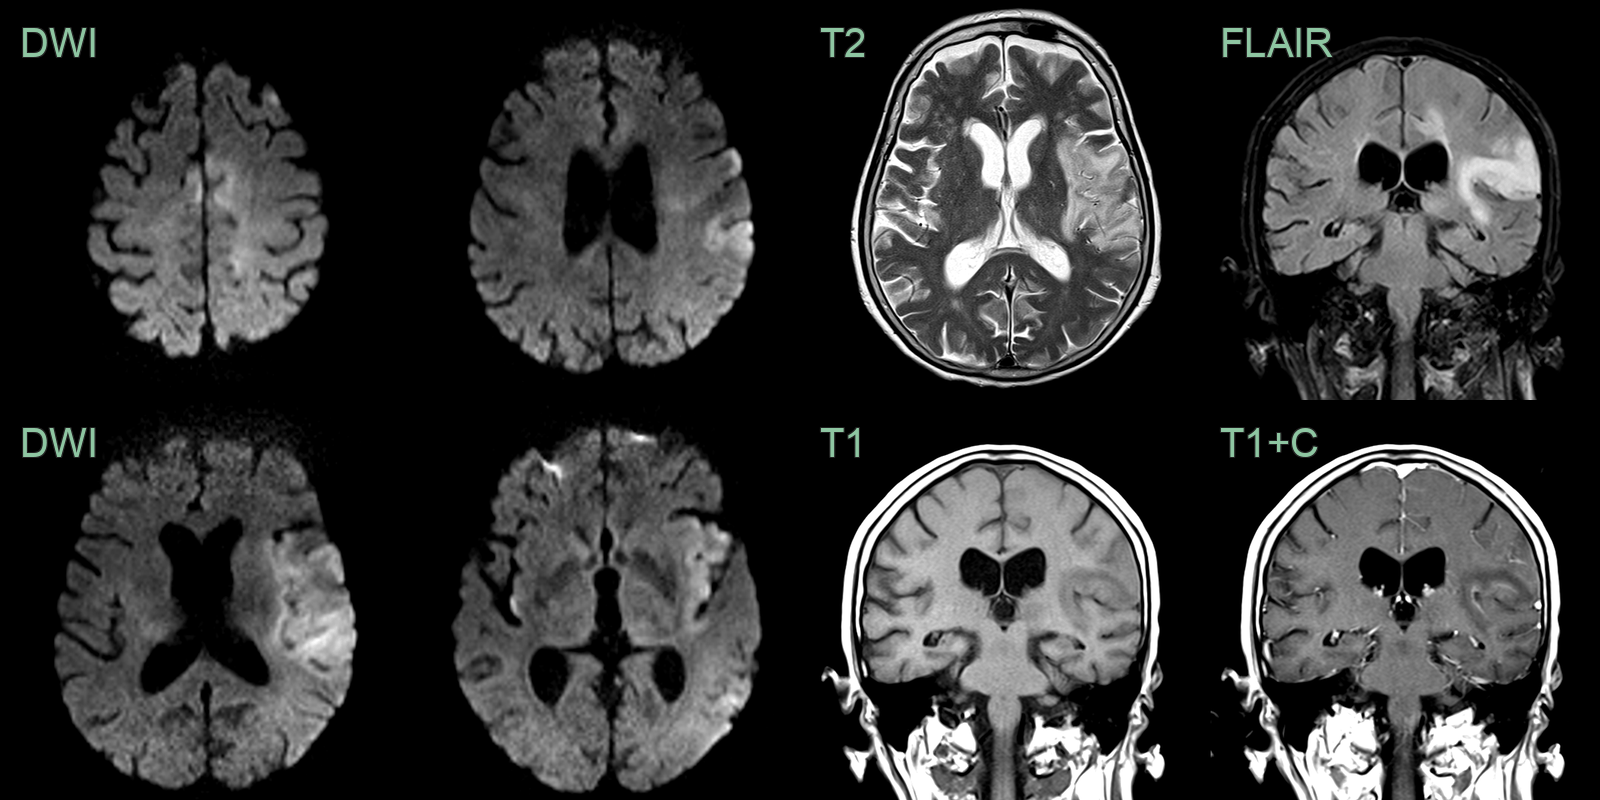

• 40-year-old patient presented with 2 day history of confusion and reduced GCS, headache and fever.

• MRI showed hyperintensity and swelling of the right mesial temporal lobe and diffusion restriction extending up to the right parietal lobe.

• 70-year-old patient presented with dysphasia and right-sided weakness and seizures. HSV was identified in CSF.

• MRI showed diffusion restriction in the cortex of left cerebral hemisphere as well as the right insula. There was swelling and subtle cortical enhancement.